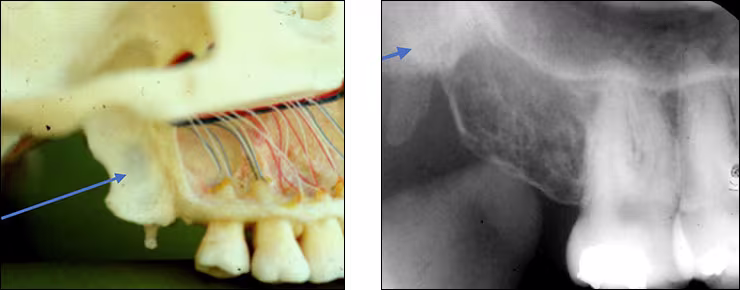

Maxillary sinus – The maxillary sinus is one of the paired paranasal sinuses. This prominent radiolucent air-filled cavity is located above the posterior teeth on the right and left sides of the maxilla. The sinus cavities are horizontally oblong bilateral structures with fine radiopaque borders. The maxillary sinus may contain septa which appear as radiopaque lines within the body of the sinus cavity. The size of the maxillary sinus can be quite variable and sometimes encroaches into the alveolar process, especially when posterior teeth are missing. Typically, the sinus appears uniform right to left. The maxillary sinus is sometimes referred to as the maxillary antrum and can be observed on both maxillary premolar and molar periapical images and partially on lateral-canine periapical images.

Zygomatic bone – The zygomatic bone or cheek bone attaches to the right and left sides of the posterior maxilla. The zygomatic bone, quadrangular in shape, broadens as it extends posteriorly. This bilateral radiopaque structure is also known as the malar bone. The zygomatic bone can be seen on maxillary premolar and molar periapical images.

Zygomatic process - The zygomatic process is the radiopaque U-shaped structure representing where the zygomatic bone attaches to the maxilla. The zygomatic process of the maxilla is the most anterior aspect of the zygomatic bone. The process is positioned toward the midline while the bone extends posteriorly away from the midline. This structure is sometimes referred to as the malar process and can be seen on maxillary premolar and molar periapical images.

Coronoid process – The coronoid process of the mandible is the triangular bony portion of the anterosuperior aspect of the ramus. This mandibular structure can be recorded on maxillary molar periapical images as the ramus moves forward when the patient’s mouth is open. It appears as a bilateral triangular or thumb-like radiopacity on posterior maxillary images. The triangular portion projects forward toward the midline. The coronoid process is the only mandibular structure recorded on maxillary molar periapical images.